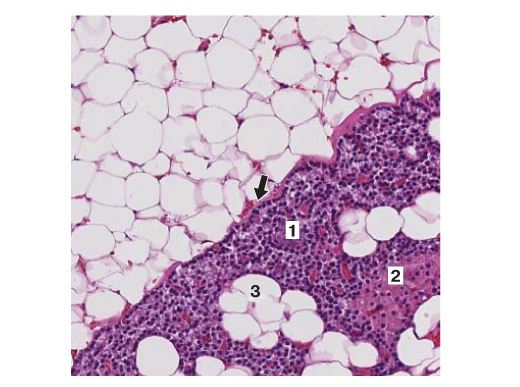

2. Fig. 2. Normal structure of OAS (staining with hematoxylin and eosin, H200). OSZHZh enclosed in a thin connective tissue capsule (arrow). The parenchyma of the gland is represented mainly by the main cells [1] in different phases of the secretory cycle, there are clusters of oxyphilic cells [2]. In the stroma, adipocytes [3] and a well-developed vascular network. | |